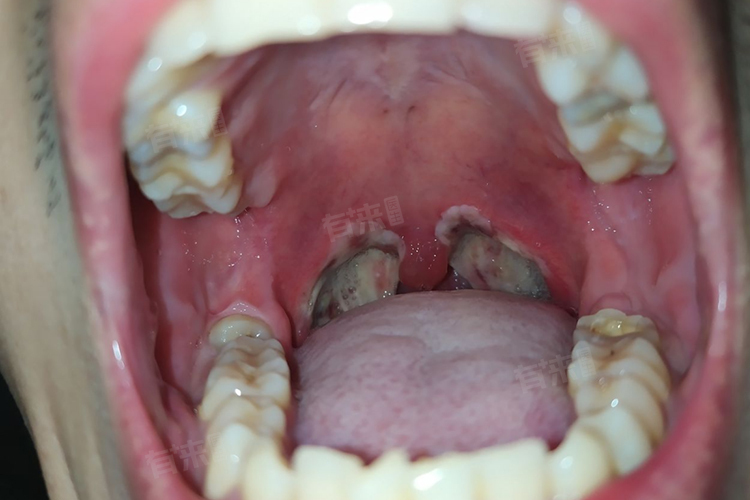

- 扁桃体手术会造成扁桃体组织缺损,术后创口处的血液、渗出的纤维蛋白以及坏死组织等混合,在创口表面形成一层白色或灰白色的膜状物,即白膜。它在术后初期起到保护创口的作用,可隔绝外界细菌、食物残渣等对创口的刺激,减少感染风险,同时为创口愈合提供一个相对稳定的环境,其存在对术后早期的创口恢复至关重要。

- 随着创口逐渐愈合,白膜会经历从形成到脱落的过程。术后3-5天,白膜生长达到稳定状态,质地较致密。之后,创口处新生的肉芽组织逐渐替代白膜,白膜开始从边缘逐渐松动、脱落。脱落过程中,新生的上皮组织会逐渐覆盖创口,完成创口的修复。这一过程是创口愈合的自然表现,也是身体组织修复能力的体现,标志着创口在逐步恢复健康。

3、密切观察恢复情况:注意口腔分泌物颜色变化,正常为淡红色逐渐转清白。创面白膜脱落期可能出现轻微异物感,属正常现象。若出现鲜红色出血、持续剧烈疼痛或发热不退等情况需立即就医。